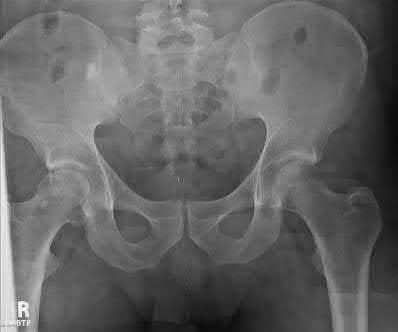

A 44-year-old male presents after being struck by a car. He is hypotensive, and has an obvious open tibia and a closed femoral shaft fracture. A pelvic radiograph is obtained and shown in Figure A. A representative CT scan image in shown in Figure B. The patient is placed in a pelvic binder, and his blood pressure normalizes with crystalloid and a blood transfusion. He then undergoes pelvic angiography, and his internal iliac artery is embolized. Which of the following definitive treatment options is most appropriate in this case?

The radiographs and CT scan show a fracture pattern consistent with an APC-III injury. This is most appropriately treated with pubic symphysis ORIF with a multi-hole plate and posterior iliosacral screw fixation.

APC-III pelvic ring injuries are associated with with disruption of the anterior and posterior SI ligaments (SI dislocation) as well as disruption of

sacrospinous and sacrotuberous ligaments. They are commonly associated with vascular injury and retroperitoneal bleeding.

Sagi et al studied the radiographic and clinical outcome of symphyseal plating techniques, specifically comparing two hole (THP) vs multi-hole plating (MHP). Retrospective review of charts and radiographs immediately after the index procedure to latest follow-up was performed. When comparing the 2 different methods of anterior fixation, they found that the rate of fixation failure was greater in group THP (33%) than group MHP (12%). When evaluating the presence of a malunion as a result of these 2 treatment methods, there were more present in the THP group (57%) than in the MHP group (15%). On the basis of these findings, the authors recommended multi-hole plating of unstable pubic symphyseal disruptions.

Grimshaw et al performed a biomechanical study to determine the failure risk and potential benefit to use of locked fixation constructs in simulated pelvic ring injuries. The authors used a six-hole 3.5-mm plate specifically designed for the symphysis pubis with the capability of fixation in locked or unlocked mode, six pelves were fixed with locked screws and six pelves were fixed standard unlocked bicortical screws. Biomechanical testing was performed, and no abrupt failures were noted. However, locked plating of the pubic symphysis did not appear to offer any advantage over the standard unlocked technique

Illustrations A, B, and C show the AP, outlet, and inlet postoperative radiographs.

Incorrect Answers:

1,4-Anterior pelvic fixation is typically not used as definitive treatment of these injuries unless performed in a damage-control setting. The patient in this case is stable.

2-Multi-hole plate fixation of the pubic symphysis is preferred over 2-hole plate fixation.

5-Posterior sacral plating is not indicated in this fracture pattern, as there is no significant sacral comminution of vertical shear component. Furthermore, no distinct advantage has been found with locked symphyseal plating.